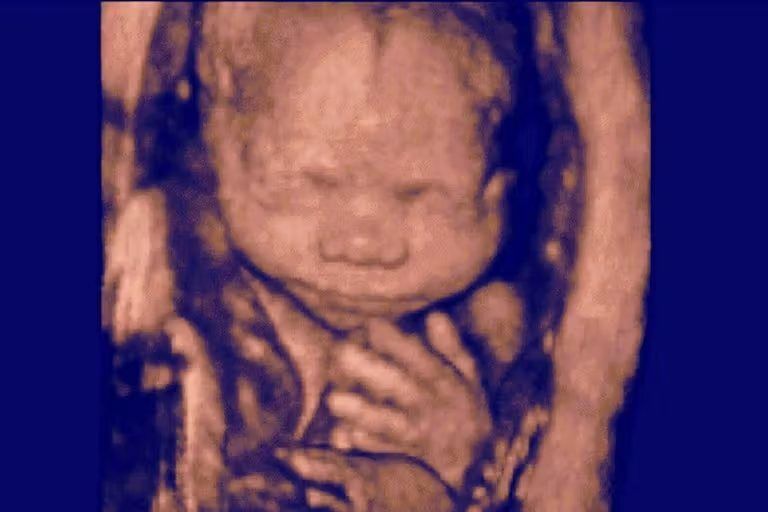

An amniocentesis verified that the baby was not genetically related to the couple. According to the lawsuit, “Ms. Doe and Mr. Doe did not know what to do. They had grown to love this baby, who had already begun kicking. On the one hand, they did not want to lose her even if she was not genetically related to them. On the other hand, they could not imagine carrying a stranger’s baby to term, only to potentially lose her in later legal battles to her biological parents, which would be devastating to the entire family.”

On December 1, 2021, they aborted the baby they claimed to love because they feared the baby’s biological parents might want her.

The most common abortion procedure at six months is a D&E abortion and involves the direct dismemberment of the child — tearing her arms and legs from her torso before crushing her skull. Another later abortion procedure called induction abortion involves injecting a drug to cause the child to go into cardiac arrest before a preterm delivery of the stillborn baby is carried out. The baby’s body is then disposed of with medical waste.